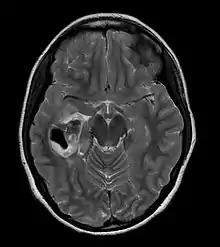

| CT scan of a brain with pleomorphic xanthoastrocytoma. The classic radiographic appearance is one of a superficially situated tumor, here a mural nodule, associated with an underlying cyst. |

Pleomorphic xanthoastrocytoma usually develops within the supratentorial region (the area of the brain located above the tentorium cerebelli). It is generally located superficially (in the uppermost sections) in the cerebral hemispheres and involves the leptomeninges. It rarely arises from the spinal cord.

These tumors are formed through the mitosis of astrocytes. They are found in the area of the temples, in the brain's frontal lobe or on top of the parietal lobe. In about 20% of cases, tumors exist in more than one lobe.